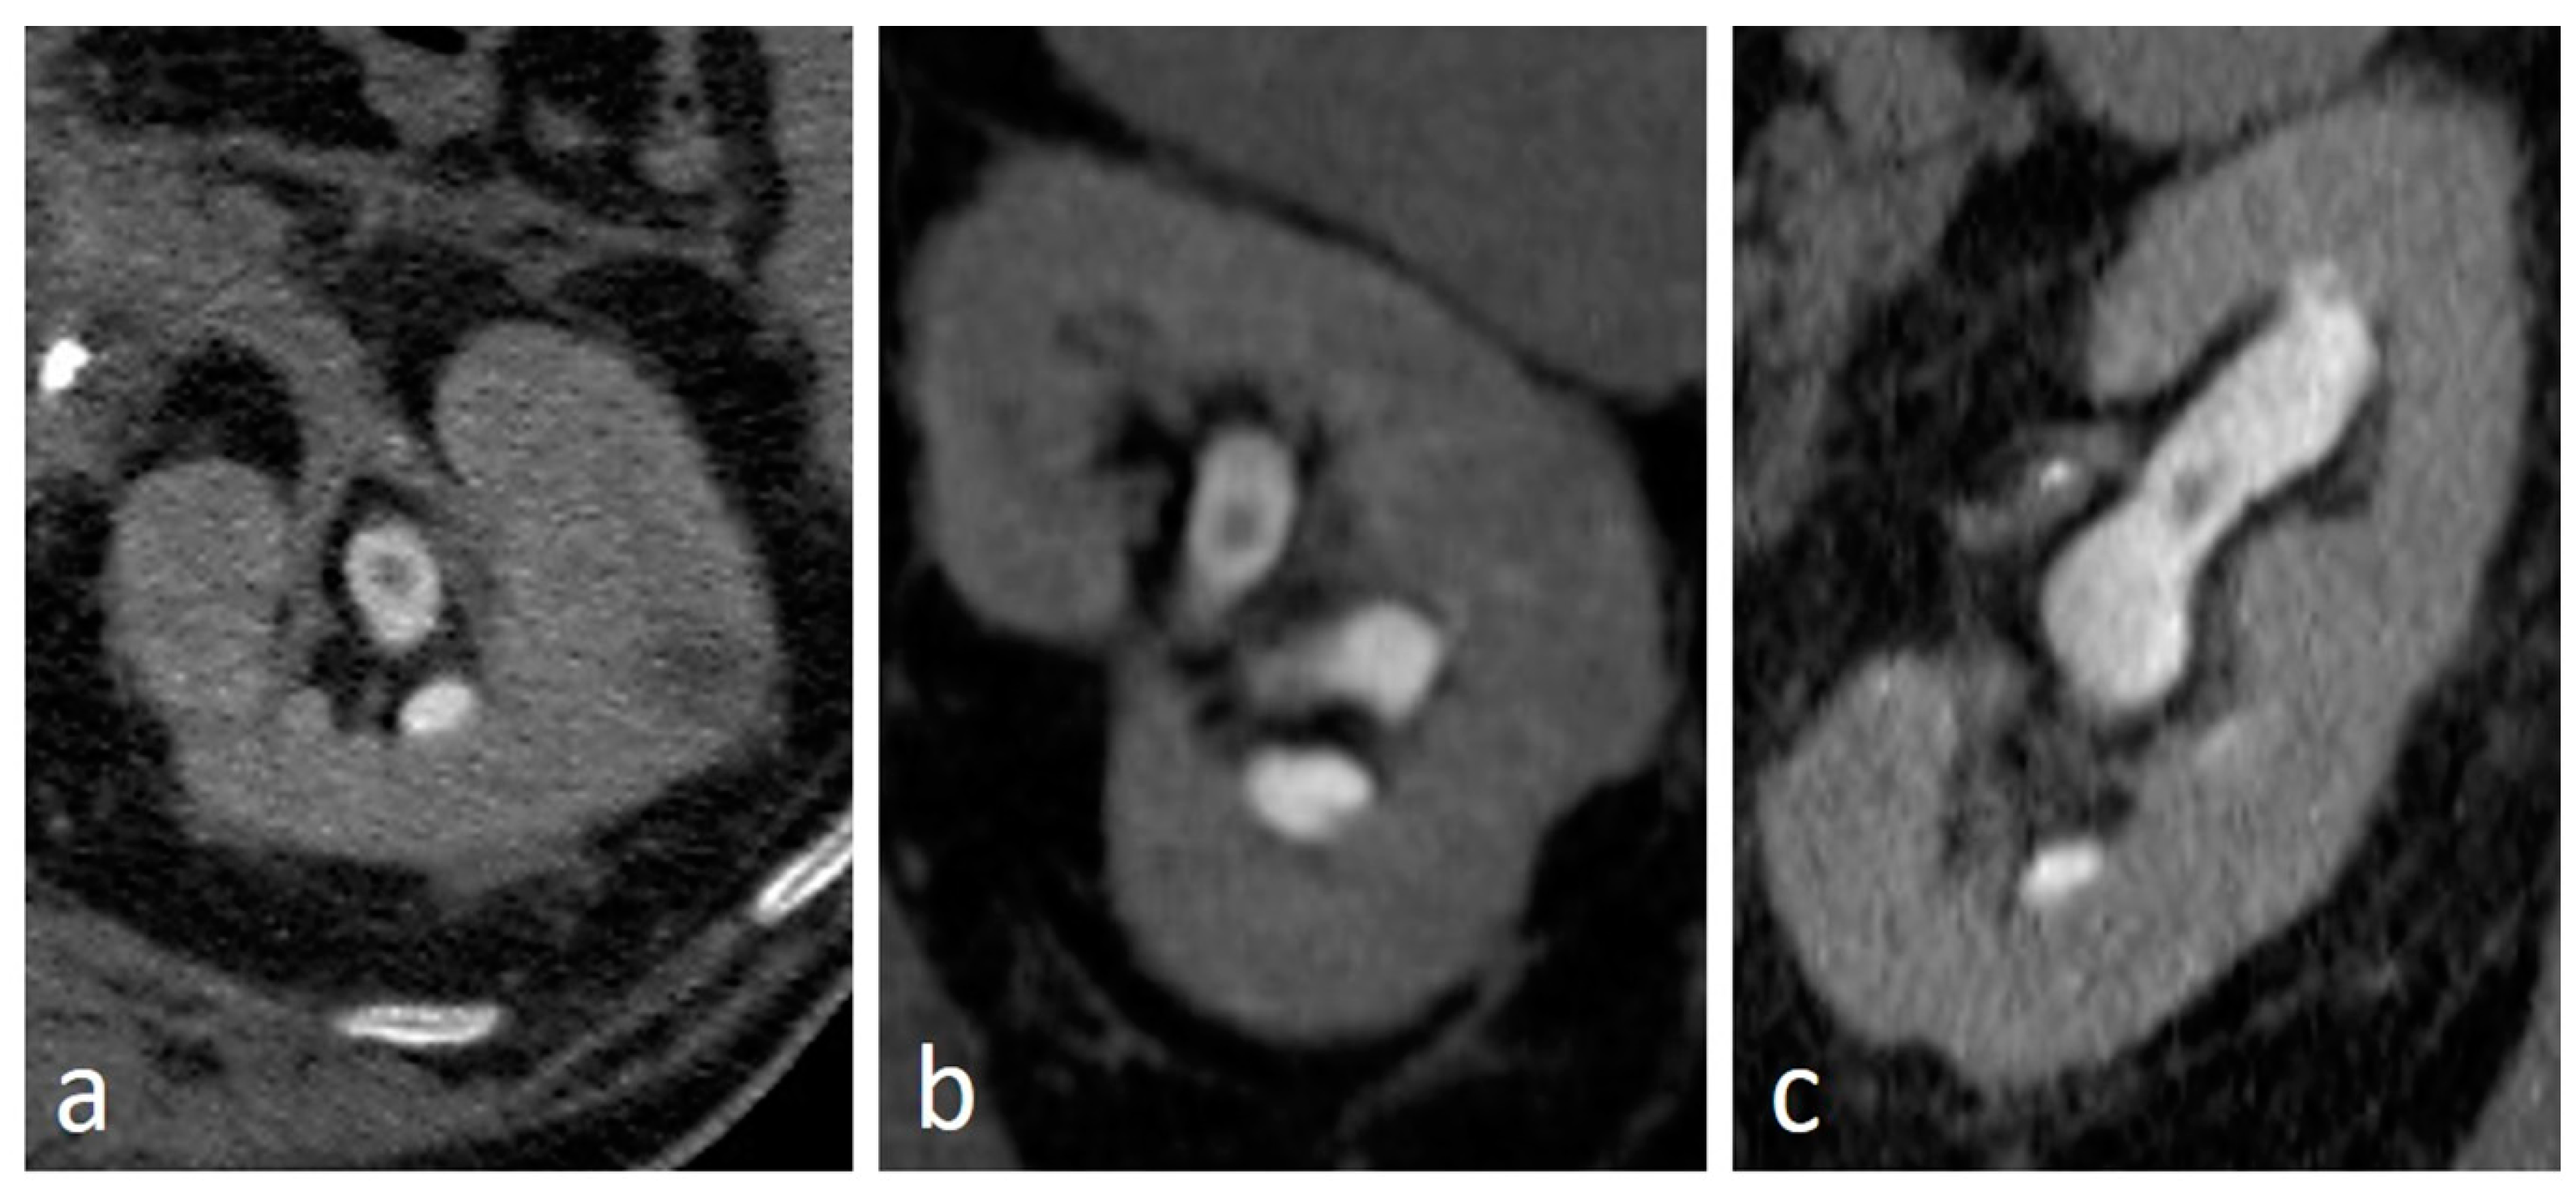

4.7. Pyeloureteritis Cystica

4.9. Fibroepithelial Polyp